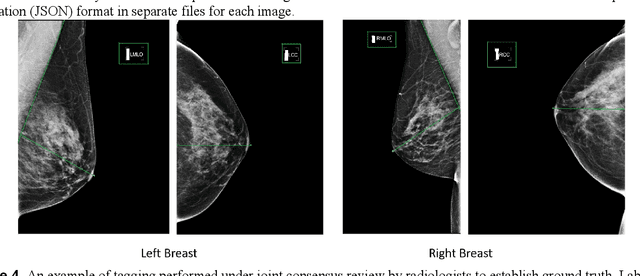

Abstract:Screening mammograms are a routine imaging exam performed to detect breast cancer in its early stages to reduce morbidity and mortality attributed to this disease. In order to maximize the efficacy of breast cancer screening programs, proper mammographic positioning is paramount. Proper positioning ensures adequate visualization of breast tissue and is necessary for effective breast cancer detection. Therefore, breast-imaging radiologists must assess each mammogram for the adequacy of positioning before providing a final interpretation of the examination; this often necessitates return patient visits for additional imaging. In this paper, we propose a deep learning-algorithm method that mimics and automates this decision-making process to identify poorly positioned mammograms. Our objective for this algorithm is to assist mammography technologists in recognizing inadequately positioned mammograms real-time, improve the quality of mammographic positioning and performance, and ultimately reducing repeat visits for patients with initially inadequate imaging. The proposed model showed a true positive rate for detecting correct positioning of 91.35% in the mediolateral oblique view and 95.11% in the craniocaudal view. In addition to these results, we also present an automatically generated report which can aid the mammography technologist in taking corrective measures during the patient visit.